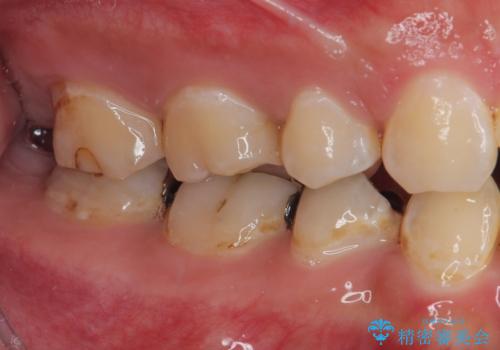

- 当院にて矯正治療を終えた患者様で銀歯を白くしたいとのことで来院された患者様です。神経の反応を確認し詰め物の範囲も大きいためフルジルコニアクラウンにて治療を行うことにしました。

拡大鏡視野下でメタルインレー、虫歯を除去しフルジルコニアクラウンに適した形に整えました。

歯と歯茎の間に圧排糸と言われる糸を入れてシリコーン印象材にて型どりをしました。